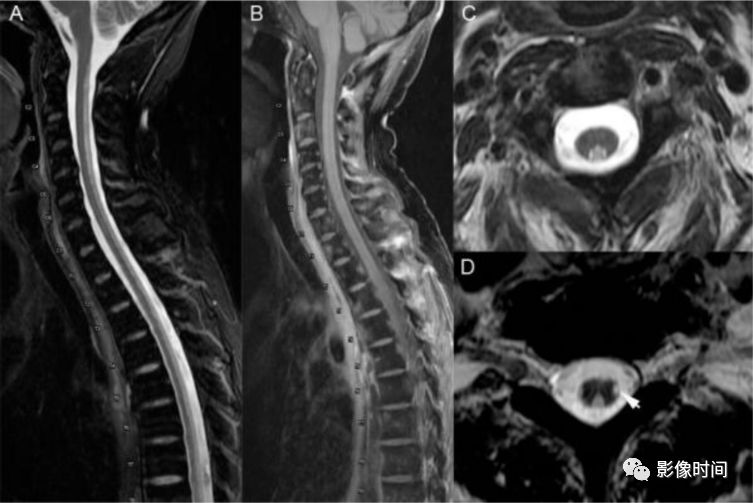

神经脊髓炎谱系疾病(neuromyelitis optica spectrum disorder,NMOSD):是一种由水通道蛋白-4(AQP-4)自身抗体介导的炎性脱髓鞘疾病,青年或中年女性较多见,临床常为双侧视神经炎和脊髓炎导致失明和截瘫,也可累及大脑。

MRI:

脊髓:病灶 T2WI 呈高信号,T1WI 呈稍低信号,急性期出现斑片状或云雾状强化,轴位常位于脊髓中央,长度>3 个椎体长度。亮点征:轴位 T2WI 很高信号的多发斑点,信号高于脑脊液,特异性=97%。

病灶分布于脊髓中央,长度大于3个椎体,亮点征

多发性硬化(Multiple sclerosis,MS)亦是一种严重的中枢神经系统自身免疫脱髓鞘病变,免疫球蛋白分泌 B 细胞和浆细胞的克隆性扩增,可使 CSF 中出现寡克隆带特征。

脊髓:颈髓较常受累,病灶 T2WI 呈高信号,T1WI 呈稍低信号,轴位常分布于前索、侧索或者后索,长轴 ≤ 2 个连续阶段椎体,急性期呈斑片状、结节状或环形强化。

病灶位于侧索、长度小于3个椎体节段